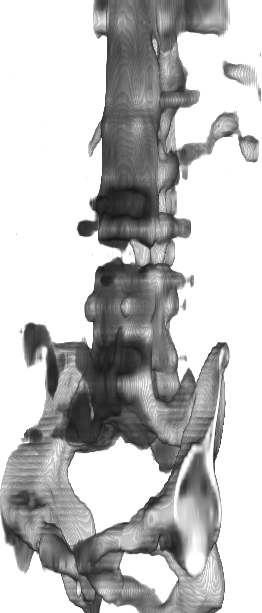

Figure 1: 3D renderings of bones from CT slice interpolation results. Bicubical interpolation (a) from sparsely sampled CT volume, with highly unrealistic distortions. Methods (b) and (c) improve the image quality; however, they are still under-resolved as is evident on the spinal column. SAINT (d) resolves details much better on the spinal column.

CT image acquisition is much faster than MRI; however, due to the high cost of keeping complete 3D volumes in memory and print, typically only necessary number of slices are stored. As a result, most medical imaging volumes are anisotropic, with high within-slice resolution and low between-slice resolution. The inconsistent resolution leads to a range of issues, from unpleasant viewing experience to difficulties in developing robust analysis algorithms. Currently, many datasets [9, 19, 1] use affine transforms to equalize voxel spacing between volumes, which may introduce significant distortions to the original data, as shown in Fig. 1(a). Therefore, methods for some analysis tasks, e.g. lesion segmentation, have to resort to intricate algorithms to take into account of the change in resolution[18, 22, 16]. As such, an accurate and reliable 3D SISR method to upsample the low between-slice resolution, which we refer to as the slice interpolation task, is much needed.

SAINT then introduces a Residual-Fusion Network (RFN) that eliminates the inconsistencies resulting from applying AMI (which addresses images in 2D) to 3D CT images, and incorporates information from the third axis for improved modeling of 3D context. Benefited by the effective interpolation of AMI, RFN is lightweight and converges quickly. Combining AMI and RFN, SAINT not only significantly resolves the memory bottleneck at inference time, allowing for deeper and wider networks for 3D SISR, but also provides improved performance, as shown in Fig. 1.